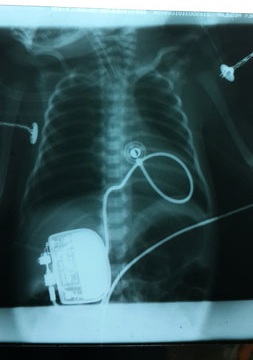

Các bác sĩ Bệnh viện Nhi Trung ương đã áp dụng kỹ thuật cấy máy tạo nhịp tim để cứu sống bé sơ sinh Trần Văn Duyệt mắc bệnh nhịp tim chậm

và sau khi được cấy máy tạo nhịp tim

Hình ảnh X-quang của bé Duyệt trước khi phẫu thuật